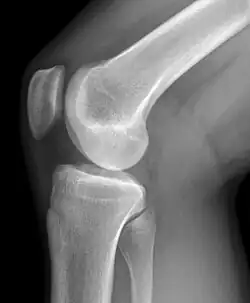

Das Kniegelenk (lateinisch Articulatio genus) ist das im Knie (lateinisch Genu, altgriechisch γόνυ gony) befindliche größte Gelenk der Säugetiere. Der Oberschenkelknochen (Femur), das Schienbein (Tibia) und die Kniescheibe (Patella) bilden dabei die knöchernen Gelenkkörper.

Das Kniegelenk ist ein zusammengesetztes Gelenk. Es besteht aus zwei Einzelgelenken, dem Kniescheibengelenk (Articulatio femoropatellaris), welches sich zwischen Oberschenkelknochen und Kniescheibe befindet, und dem Kniekehlgelenk (Articulatio femorotibialis), das zwischen Oberschenkelknochen und Schienbeinkopf (Caput tibiae) liegt. Anatomisch gesehen handelt es sich bei dem proximalen Gelenk zwischen Schienbein (Tibia) und Wadenbein (Fibula) (Articulatio tibiofibularis) zwar um ein eigenständiges Gelenk, das aber in der Regel über eine Ausbuchtung der Kniegelenkkapsel (Recessus subpopliteus) mit dem Kniegelenk verbunden ist.

Die Gelenkflächen der Gelenkkörper sind mit hyalinem Gelenkknorpel überzogen, der sich unter der Wirkung übertragener Kräfte verformt und damit die Kontaktflächen bereitstellt, auf denen die Flächenpressdrücke das notwendige Kräftegleichgewicht herstellen. Die Gelenkflächen können nur Druckkräfte übertragen. Da in der Regel nur Teile der Gelenkflächen als Kontakt- und Tragflächen fungieren, sind die tatsächlichen Pressdrücke wesentlich höher als die aus den anatomischen Gelenkflächen geschätzten Drücke, sie übersteigen den Blutdruck um ein Vielfaches. Daher sind im Gelenkknorpel auch keine Blutgefäße, denn der Blutdruck könnte keinen Stoffaustausch gegen den Gewebedruck aufrechterhalten. Der zwischen den beiden Knorpeloberflächen liegende Gelenkspalt ist sehr dünn: lediglich einige Moleküllagen Gelenkschmiere passen hier hinein. Die Dimension des Gelenkspalts liegt im Mikrometerbereich und ist im Röntgenbild nicht darstellbar. Was der Orthopäde als „Gelenkspalt“ bezeichnet sind die beiden strahlendurchlässigen Knorpelschichten der Gelenkkörper. Der Gelenkknorpel ist von Kollagenfasern durchzogen, die ihn auf dem Knochen befestigen und ihm eine gewisse Zugfestigkeit verleihen. Am Gelenkspalt verlaufen sie in horizontaler Richtung (die sogenannte Tangentialfaserschicht) und unterstützen das Gleiten der Gelenkkörper.